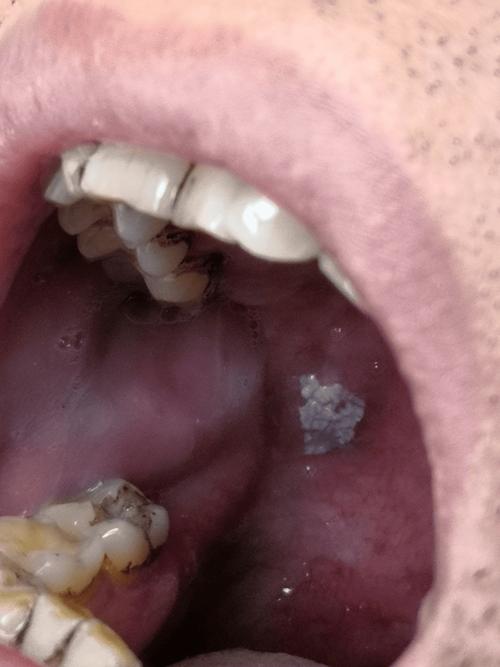

(图片来源网络,侵删)

- 疣状病变:虽然由低危型HPV引起的口腔疣(如寻常疣、尖锐湿疣)更常见,但高危型HPV在极少数情况下也可能导致口腔出现疣状病变。

- 癌前病变:持续感染可能导致口腔黏膜出现癌前病变,如果不加以干预,可能进一步发展为癌症。